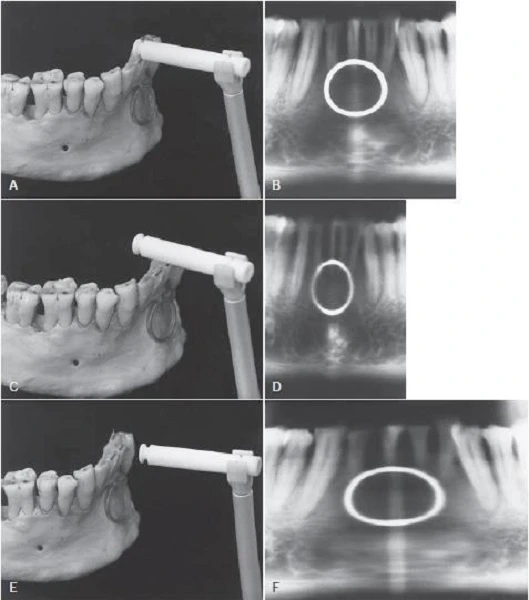

Hình 7, từ A đến F, minh họa ảnh hưởng của vị trí bệnh nhân đến kích thước và hình dạng của hình ảnh. Hình 7, A đến B cho thấy một xương hàm dưới và một vòng làm bằng đồng nằm ngay chính giữa lớp ảnh. Lưu ý là sự phóng đại bằng nhau giữa vòng kim loại và hình ảnh các răng trước theo cùng một tỉ lệ. Hình 7 từ C đến D của cùng xương hàm dưới đó được đặt về phía trước 5mm so với trọng tâm của lớp ảnh. Vị trí này gây ra sự biến dạng vòng theo chiều ngang, vòng mảnh hơn và tương ứng với sự giảm chiều rộng hình ảnh răng.

Hình 7 từ E đến F của cùng xương hàm dưới đó nhưng được đặt về phía sau 5 mm so với giữa máng tiêu cự. Bây giờ biến dạng theo chiều ngang với kết quả vòng rộng hơn và tương ứng với sự tăng độ rộng của răng được chụp. Trên những hình ảnh này kích thước theo chiều dọc, ngược với kích thước theo chiều ngang bị thay đổi một ít, mặc dù nhìn có vẻ như vậy. Những biến dạng này là kết quả từ chuyển động thuận nghịch theo chiều ngang của thụ thể và nguồn tia X.

Vì vậy, như quy luật chung, khi cấu trúc quan tâm, chẳng hạn như trong trường hợp này là xương hàm dưới, bị thay đổi đến mặt trong so với vị trí tối ưu của lớp ảnh, hướng về phía nguồn tia X, tia xuyên chậm qua nó hơn tốc độ mà thụ thể di chuyển.

.

Do đó, những hình ảnh cấu trúc trong vùng này bị kéo dài theo chiều ngang và trên ảnh chúng xuất hiện rộng hơn. Ngoài ra, khi xương hàm dưới bị thay đổi vị trí hướng về phía mặt ngoài của lớp ảnh, tia đi ngang qua với tỉ lệ nhanh hơn so với khi xuyên qua cấu trúc. Trong dẫn chứng đưa ra, vì thụ thể di chuyển với một tốc độ chính xác, hình dạng của các răng trước bị nén theo chiều ngang trên ảnh, và chúng xuất hiện mảnh hơn.

Chú ý đặc biệt cho phần này khi có sự tiến triển của tổn thương ở xương, đặc biệt là vùng răng trước. Vì vị trí của bệnh nhân không đúng, tổn thương có thể xuất hiện lớn hơn hoặc nhỏ hơn so với hình ảnh đúng. Do đó, tầm quan trọng của việc chuẩn bị vị trí cung răng bệnh nhân trong vùng ảnh là điều hết sức rõ ràng.